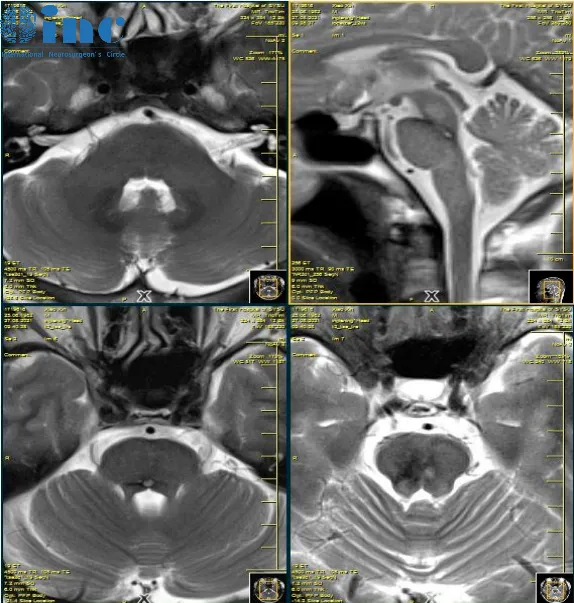

对于很多脑干海绵状血管瘤患者而言,巴教授甚至评估无需手术。39岁的佟先生,2019因脑干出血导致手麻,嘴麻,头麻,复视,站不稳,诊断为桥脑海绵状血管瘤。2021年,脑干再次出血,需要手术吗?

巴教授评估回复

“没有发现任何手术指征,一年一次的MRI复查是足够的!因为没有可以通过手术切除的活动性海绵状血管畸形。再次出血的风险或MRI出现一些显著变化的概率极低。”